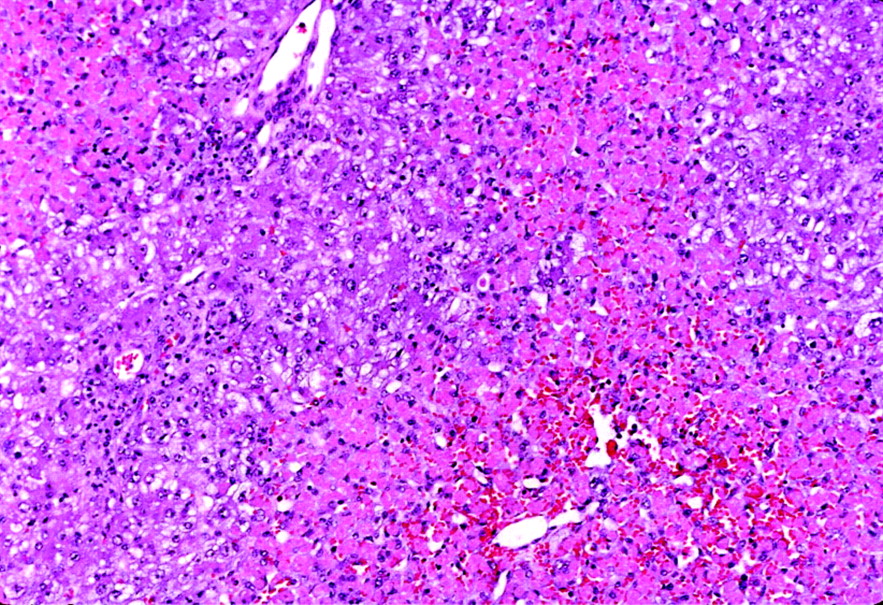

HISTOPATHOLOGY REPORT IN CCl 4 INDUCED HEPATOTOXICITY Negative

HISTOPATHOLOGY REPORT IN CCl 4 INDUCED HEPATOTOXICITY Negative Acetaminophen Hepatotoxicity Histology It is safe when taken at therapeutic doses; However, due its wide availability, it is frequently implicated in. Describe the clinicopathologic features of excessive acetaminophen ingestion focusing on biochemical. Acetaminophen (apap) is an antipyretic and analgesic drug that is commonly known as paracetamol, an ideal hepatotoxicant to. Acetaminophen (apap) overdose is the clinically most relevant drug hepatotoxicity in western countries,. Acetaminophen Hepatotoxicity Histology.